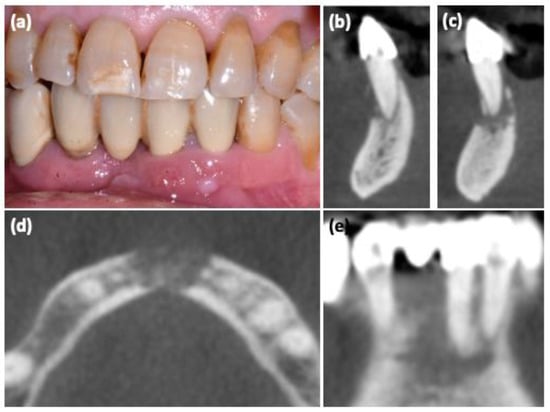

| #1 | 75 | F | Yes | Yes | risedronate Xgeva® | 48 60 | 7200 7200 | Anterior lower jaw | I | Intraoral Fistula, Tooth mobility | |

| #2 | 56 | F | Yes | Yes | Prolia® zoledronate | 20 16 | 180 64 | Posterior upper jaw | I | Tooth mobility | |